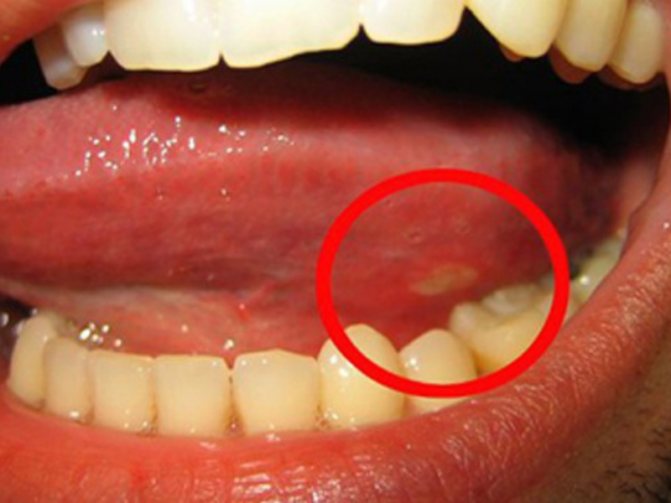

Лейкоплакия – заболевание, характеризующееся поражением слизистых оболочек, ороговением покровного эпителия разной степени выраженности. Первые и главные ее причины – это курение и алкоголь, а также реакция слизистой оболочки на разнообразные внешние раздражители, которая развивается на фоне действия различных эндогенных факторов и прежде всего желудочно-кишечной патологии, выявляемой у 90% больных.

Локализуется на слизистой оболочке нижней губы, угла рта, дна полости рта, языка, щек (в двух последних случаях чаще располагается по линии смыкания зубов). Встречается обычно в возрасте около 30 лет. Внешними раздражителями, непосредственно вызывающими лейкоплакию, служат хроническая механическая травма, горячий табачный дым, инсоляция и другое.

Течение лейкоплакии хроническое. Если раздражающий фактор устранен или его действие резко ослаблено, если проведена санация организма в широком смысле слова, то прогрессирование лейкоплакии обычно прекращается, и при правильной консервативной терапии она может регрессировать. Иначе заболевание постепенно прогрессирует и может трансформироваться в рак, что происходит при веррукозной и эрозивной форме.